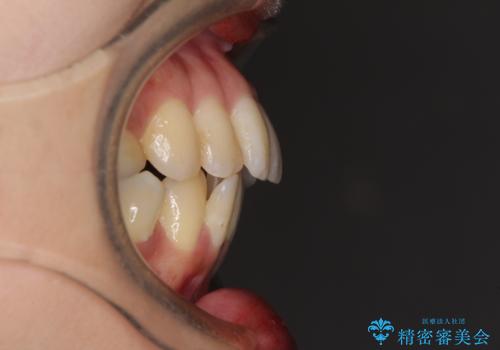

後戻りで突出した前歯をインビザラインで解消

- 抜歯矯正の後戻りで前歯が突出してきていることを気にして来院された患者様です。

口元の突出感を改善するにあたり、抜歯矯正は行うことができないため、奥歯の後方移動とIPR(歯と歯の間を削る)により達成することとしました。